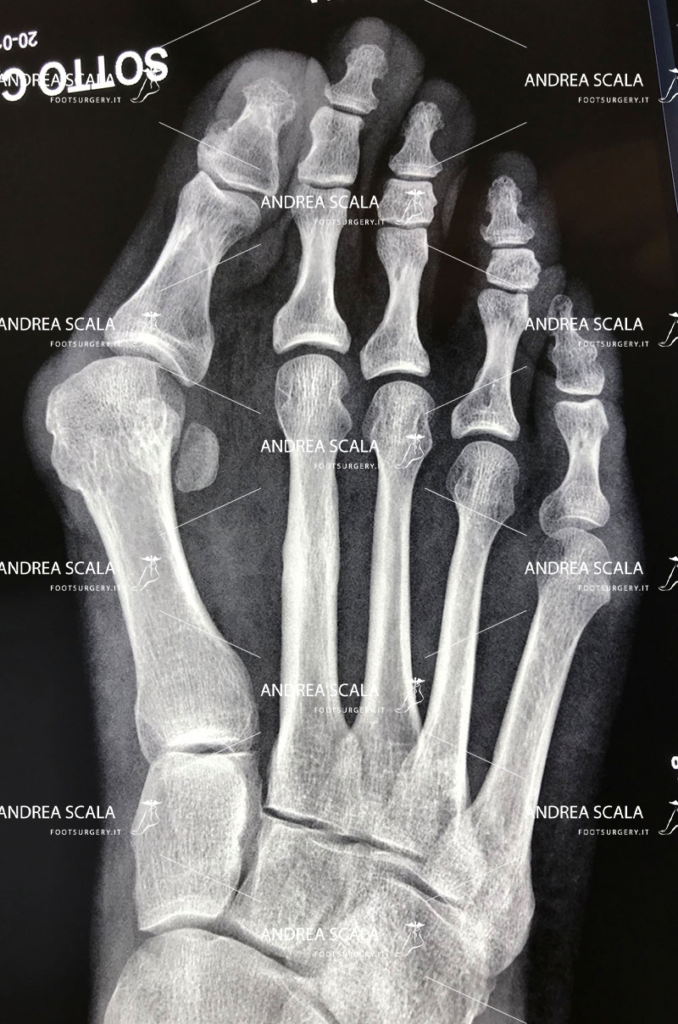

Con il termine “alluce valgo” ci si riferisce a una patologia che non colpisce propriamente solo l’alluce, ma tutta la parte anteriore del piede. Molto semplicemente, si tratta di una deviazione dell’alluce verso l’interno, ovvero verso le altre dita, che causa un particolare rigonfiamento laterale in corrispondenza della testa del primo metatarso.

Questa tencnica prevede l’uso di un frullino che viene messo sotto la pelle della paziente (percutanea). Il chirurgo quarda la Rxgrafia, ma non osserva con gli occhi ciò che sta facendo sotto la pelle (percutanea). Il frullino ad alta velocità taglia l’osso e alcune volte anche tendini, vasi e nervi. Al termine dell’intervento l’osso tagliato viene lasciato libero di guarire senza alcun sostegno e senza alcuna guida. Osserviamo in ambulatorio casi molto gravi in cui l’osso è guarito storto o non si è più riattaccato.

L’operazione dell’alluce eseguita con tecnica mininvasiva (con una minima incisione).

Il dott. Andrea Scala ha messo a punto una tecnica, pubblicata in U.S.A. nel 2013 che supera i problemi che la tecnica percutanea comporta.

Grazie a questa tecnica è possibile sezionare l’osso deformato per riposizionarlo e riallinearlo con le altre dita del piede, il tutto effettuando solo un’incisione di pochi millimetri sulla cute. La minima incisione taglia l’osso con precisione ed evita di tagliare anche tendini, vasi e nervi. Al termine dell’intervento un piccolo chiodo di 1 millimetro aiuta l’osso tagliato a guarire nella posizione corretta e assicura che l’alluce operato non tornerà mai più.